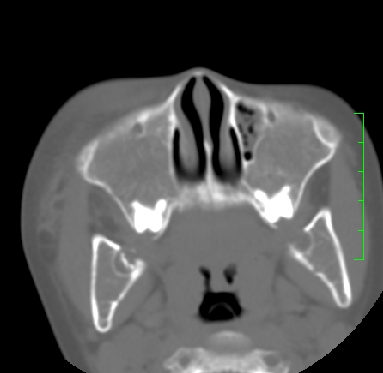

标题: PED1889:上颌窦病变

m,10y,外伤做ct

骨化性纤维瘤可能性大。(与骨纤的鉴别:常见于面颅骨,多骨发病)